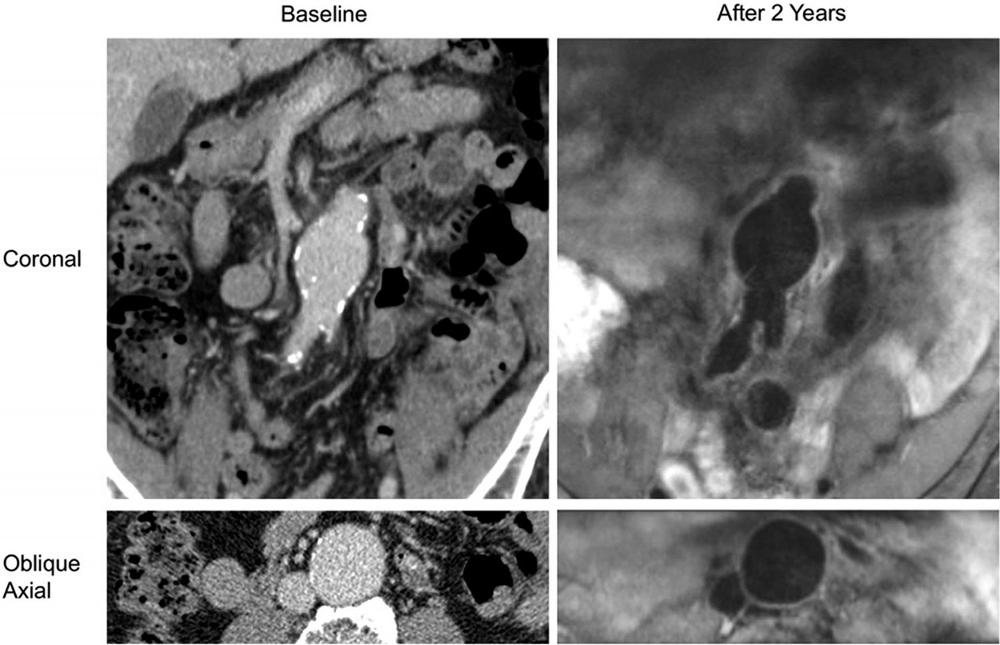

Figure 6. A patient (aged 83 years, male) who was followed up with black-blood MRI. The abdominal aortic aneurysm had no intraluminal thrombus at baseline or follow-up. Coronal and oblique axial contrast-enhanced CT images show that the aneurysm had a 4.0-cm diameter at baseline; 2 years later, black-blood MRI shows that the aneurysm grew to 4.2 cm at a growth rate of 1 mm/y.

High-res (TIF) version